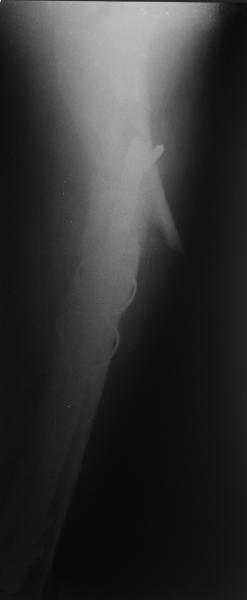

Изначально была выбрана не правильная точка введения стержня, в связи с чем в конце, я подчеркну, в конце операции произошло из-за напряжения между прокимальным концом канала бедра и стержнем разрушение в/3 бедра.

Проволока наложена потому, что при введении штифта не прошли эту зону римером и произошли сколы на концах отломков.

Под ЭОП во время операции такого смещения не было. Мы бы конечно не отпустили этого больного с такой картиной (сами бы что-то сделали или к вам отпр).

Зона раскола во время моей ревизии проходит по боковой поверхности как раз в зоне введения шеечного винта (картина как топор разрубил полено на две равных части, можа сделать КТ?)